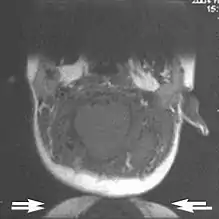

Metal artifacts

Metal artifacts occur at interfaces of tissues with different magnetic susceptibilities, which cause local magnetic fields to distort the external magnetic field. This distortion changes the precession frequency in the tissue leading to spatial mismapping of information. The degree of distortion depends on the type of metal (stainless steel having a greater distorting effect than titanium alloy), the type of interface (most striking effect at soft tissue-metal interfaces), pulse sequence and imaging parameters. Metal artifacts are caused by external ferromagnetics such as cobalt containing make-up, internal ferromagnetics such as surgical clips, spinal hardware and other orthopaedic devices, and in some cases, metallic objects swallowed by people with pica.[3] Manifestation of these artifacts is variable, including total signal loss, peripheral high signal and image distortion (Figs 3 and 4).[1] Reduction of these artifacts can be attempted by orientating the long axis of an implant or device parallel to the long axis of the external magnetic field, possible with mobile extremity imaging and an open magnet. Further methods used are choosing the appropriate frequency encoding direction, since metal artifacts are most pronounced in this direction, using smaller voxel sizes, fast imaging sequences, increased readout bandwidth and avoiding gradient-echo imaging when metal is present. A technique called MARS (metal artifact reduction sequence) applies an additional gradient, along the slice select gradient at the time the frequency encoding gradient is applied. ==Signal processing dependent artifacts== The ways in which the data are sampled, processed and mapped out on the image matrix manifest these artifacts.[1]